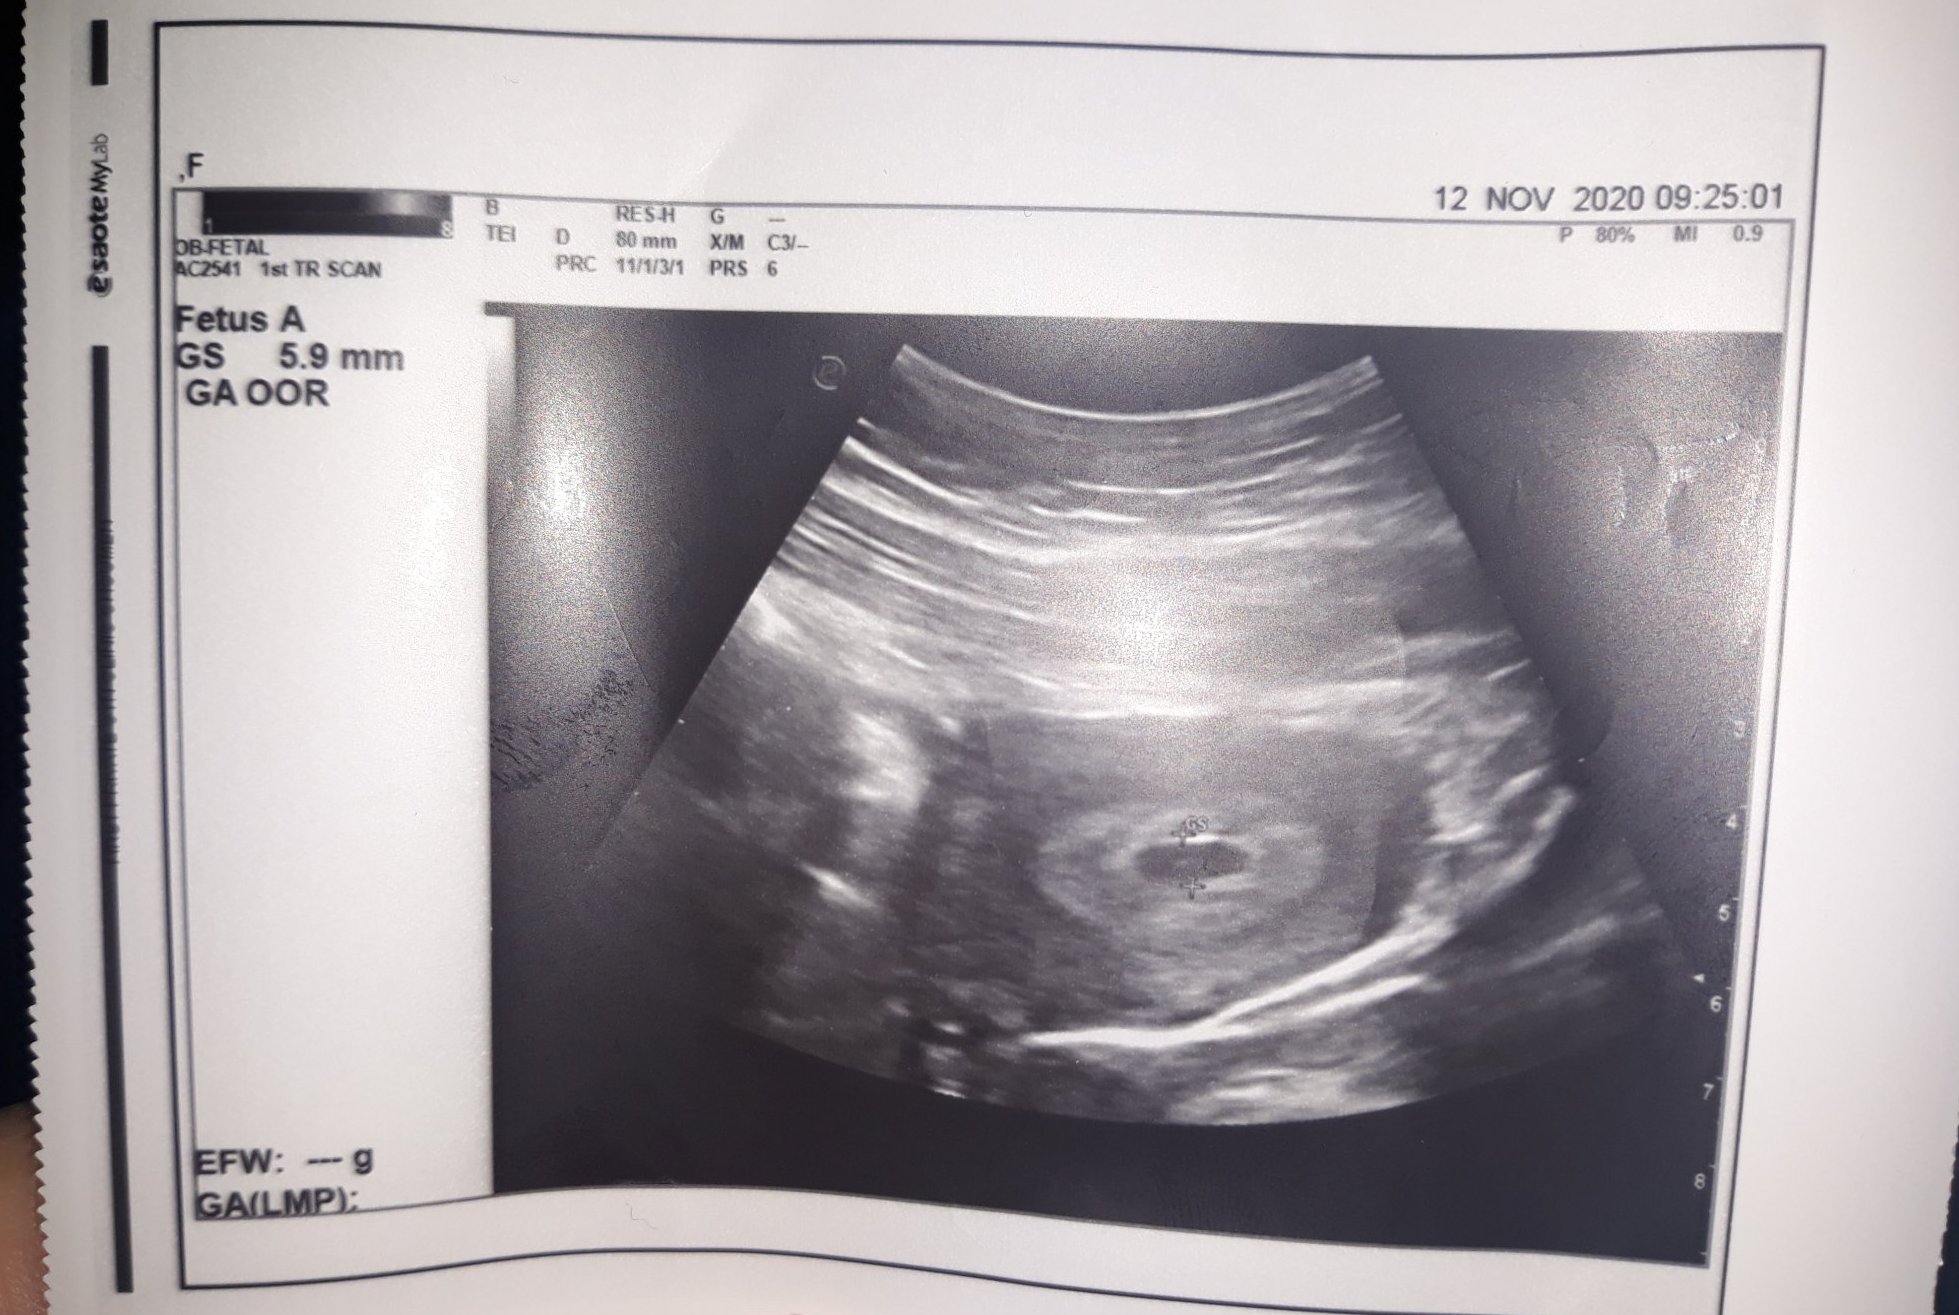

И моят преглед при гинекологът,който съм избрала мина днес. Видяхме отново плодното сакче, отговарящо на 5 г.с. За зацапването, което имах преди дни ми изписа Утрогестан, но каза че за сега всичко е наред. Ето и една снимчица.